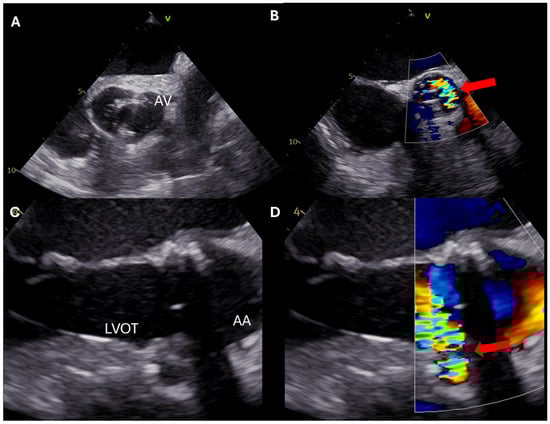

| AV repair | Describe mechanism of AR Define feasibility of repair Image coronary vessels Image ascending aorta | Ensure no/mild residual AR Exclude persistent prolapse Estimate durability of repair (measure coaptation length) |